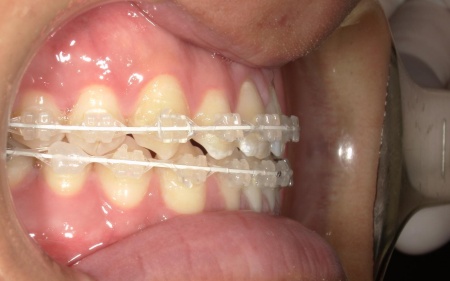

②白色(セラミック)のブラケットとホワイトワイヤーを用いたセラミックブラケット矯正

矯正の方法は①と同様ですが、装置の色味が異なります。

メリット:装置が白いため歯の色に馴染みやすく、目立ちにくい

デメリット:色の濃い飲食物で、装置が変色するおそれがある

患者様は「できるだけ目立ちにくい装置を使用したい」とのことから、②のセラミックブラケット矯正を選択されました。

まず、下奥歯(臼歯)を歯茎の外側に持ち上げる「挺出(ていしゅつ)」という処置を行いました。

奥歯が少し高くなることで、下顎全体がわずかに後ろへ動くため、前歯の噛み合わせが整いやすくなります。

加えて、上下の前歯には「IPR」という処置を行いました。これは、歯の表面のエナメル質をごくわずかに削り、歯を動かすためのスペースを作る方法です。

このスペースを利用して前歯を後方へ移動させ、審美性の改善を目指しました。

最後に、歯並びと噛み合わせが整い、見た目にも問題がないことを確認し、治療を終了しています。